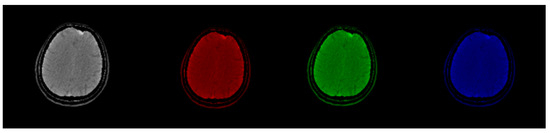

3.1. CIT Application

3.2. Colormap Folding Application